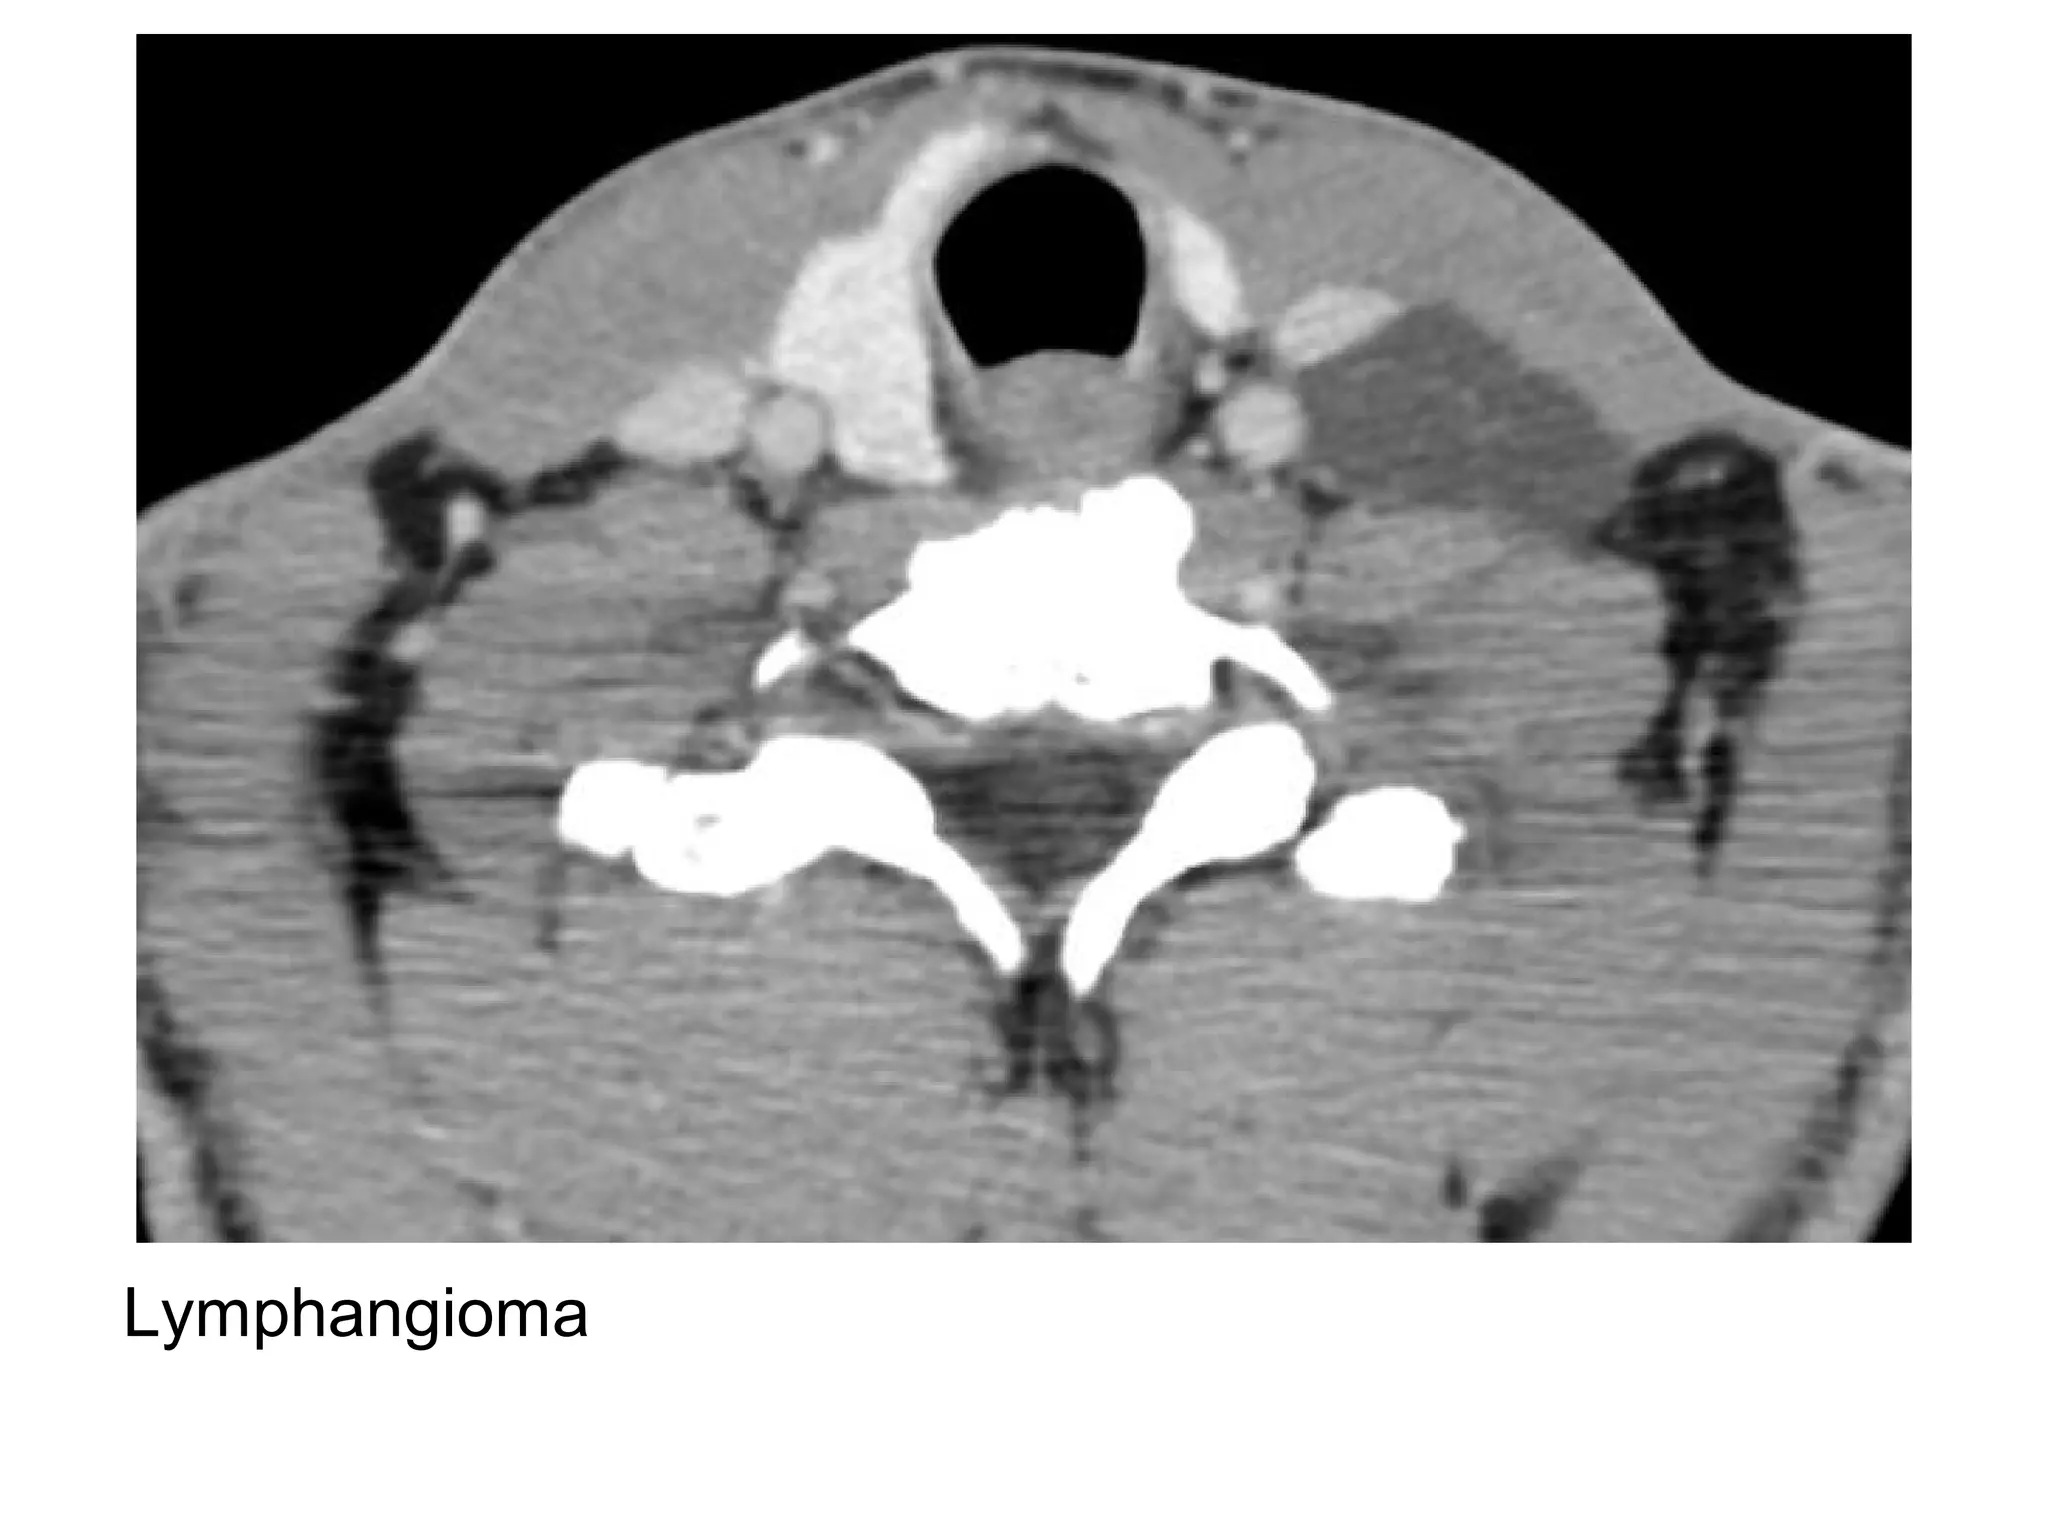

Lymphangioma